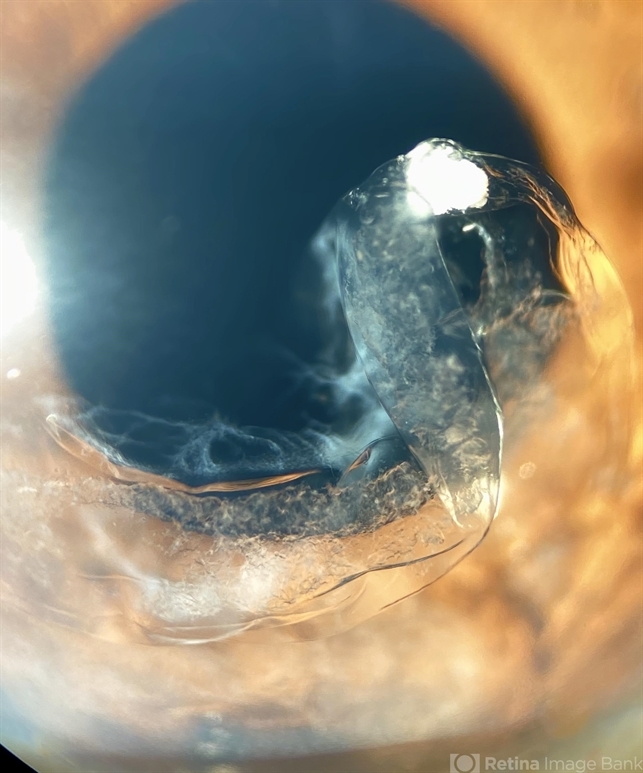

- anterior dislocation of lens, dropped capsular IOL bag complex, anterior segment, anterior chamber, cataract surgery

- Manuel Ángel Alcántara Delgado, CMN SXXI, Mexico City

- Photo slit lamp biomicroscope

- Slit lamp photograph of a 65-year-old woman with previous history of complicated cataract surgery.